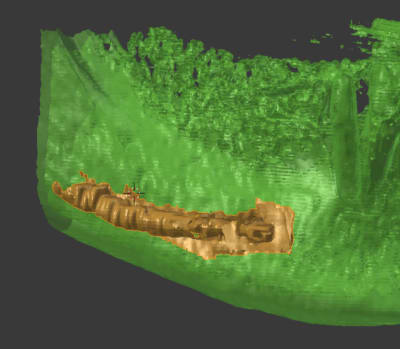

ton image Drmarcus me rappelle qu'il faut que je mette un indicateur pour la distance entre les implants

les coupes de 1.5mm dont je parlais

en marron crème la position des fx moignons